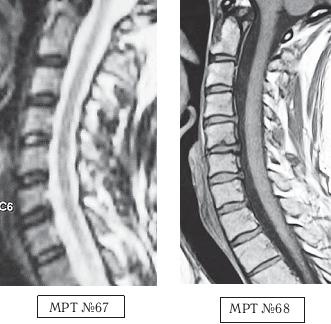

На МРТ № 67 от 17.09.2009 наблюдается шейный отдел позвоночника с признаками формирования протрузий в сегментах CV—CVI, CVI—CVII. Физиологический лордоз сохранён, признаков нарушения проводимости ликворных путей не наблюдается.

На МРТ № 68 от 12.10.2009 у той же пациентки наблюдается значительное прогрессирование дегенеративно-дистрофического процесса в шейном отделе позвоночника с осложнениями в виде грыж межпозвонковых дисков CIV-CV, CV-CVI, CV—CVII, сглаживание физиологического лордоза с нарушением ликвородинамики.

В действительности же этим «чудом» оказался всего лишь раздвижной стол с изменяемым углом наклона для растяжения позвоночника. Со слов пациентки, её «положили на этот раздвижной стол, к нижней половине стола привязали ноги и таз в районе талии, а к верхней половине привязали голову под челюсть и затылок (очевидно петлёй Глиссона) и начали крутить какую-то ручку, стол стал раздвигаться и наклоняться вниз». После того как вследствие растяжения шейного отдела позвоночника у данной пациентки появились сильные боли, врач сказал «терпеть» и оставил её в такой «растяжке» на десять минут. После чего пояснил, что таких сеансов «вправления выпавшего диска» ей надо пройти как минимум десять и тогда всё будет хорошо. До десяти сеансов пациентка не дотянула, так как «хорошо» ей уже стало после шестого сеанса, начались синкопические состояния (состояние перед обмороком), боль и онемение в правой руке, головокружение и нарушение координации при ходьбе.

Ещё один показательный пример о том, как молодая девятнадцатилетняя девушка попала к «чудо-новатору» по методам вытяжения позвоночника. Началась данная история с того, что у молодой студентки, вследствие длительной работы на компьютере, стали появляться боли в мышцах шеи и плеч. Она обратилась к врачу. Этот «специалист» после осмотра поставил ей предварительный диагноз — «смещение диска» и направил на МРТ. Заметьте, на первый взгляд врач действовал правильно, направив пациента на МРТ уточнить диагноз. Но как потом оказалось, для него это являлось всего лишь формальностью, а не установлением истинной причины происхождения болей и тем более не заботой о выборе щадящих методов лечения. Впрочем, судите сами.

После результатов обследования, в описании которого была указана только протрузия в сегменте CVI-CVII размером 1,4 мм центральной локализации, данный врач объяснил, что «это и есть смещение диска, который давит ей на нерв» и предложил его вправить, на что девушка, по своей наивности и из-за отсутствия элементарных знаний о развитии патологии в позвоночнике, согласилась. Более того, на её беду (в прямом смысле слова) этот врач оказался новатором-изобретателем. По его словам, он «совершил настоящую революцию в вертебрологии» (сам он травматолог), «изобрёл чудо-устройство, с помощью которого можно навсегда избавить пациента от остеохондроза». Я не утрирую, это действительно слова данного «специалиста». Он стал рассказывать девушке, что «изобретение» настолько эффективное, что к нему даже японцы приезжали с просьбой продать им это «чудо», но не продал (не по причине патриотизма), просто потому, что японцы хотели его обмануть и предложили слишком мало денег, «всего два миллиона евро». В данном случае вы сами понимаете, что ни о какой порядочности и врачебной этике такого «специалиста» говорить не приходится, если в голове вместо знаний науки вертебрологии только подсчёт количества нулей.